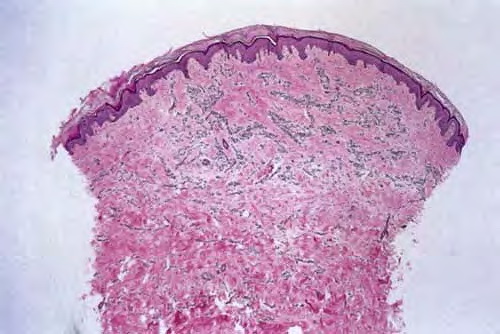

microvenular-hemangioma